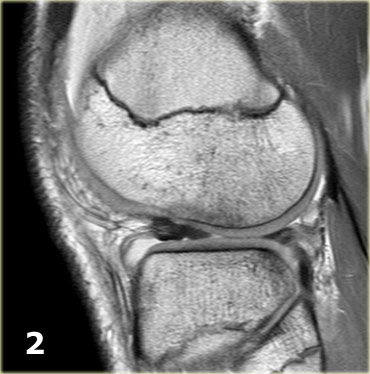

Bên trái là ba lát cắt coronal PD liên tiếp:

-

Rách bó dây chằng bên trong sâu (mũi tên vàng).

Bong mảnh xương ở mặt ngoài đầu gần xương chày, tức là gãy xương Segond (mũi tên đỏ). -

Lưu ý mảnh sụn chêm phía trong bị di lệch.

Điều này cho thấy còn có thêm rách dạng quai xô (bucket handle tear). -

Ngoài rách dạng quai xô (mũi tên xanh phía trong), còn có một đường rách ngang khó nhận thấy ở phần ngoại vi của sụn chêm (mũi tên xanh phía ngoài).

Đường rách ngang này được thể hiện rõ hơn trên các hình ảnh khác (không trình bày ở đây).

Tiếp tục xem các hình ảnh sagittal.

Gãy xương Segond gần như là dấu hiệu đặc trưng (pathognomonic) của rách dây chằng chéo trước, điều này cũng được ghi nhận ở bệnh nhân này.